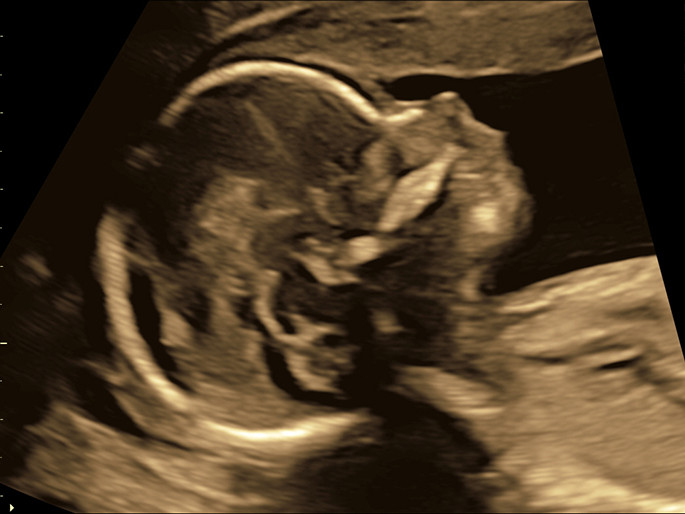

Anhand der Nackentransparenz kann zusammen mit anderen Markern (Nasenbein, Ductus venosus, Trikuspidalregurgitation) eine Wahrscheinlichkeit für das Vorliegen einer Chromosomenstörung wie z.B. der Trisomie 21 berechnet werden.

Nackentransparenz:

Die Nackentransparenz ist eine geringe Ansammlung von Flüssigkeit unter der Nackenhaut, die im Ultraschall bei allen Kindern im Zeitraum zwischen der 12+0 und 13+6 Schwangerschaftswoche (bzw. 45-84 mm Scheitelsteißlänge) messbar ist. Für die Dicke dieser Nackentransparenz gibt es für jede Schwangerschaftswoche Normwerte. Eine Verbreiterung dieser Nackenfalte kann bei Kindern mit einer Chromosomen-störungen, aber auch bei anderen Fehlbildungen wie z.B. Herzfehlern auftreten. Grundsätzlich gilt, dass mit Zunahme der Nackentransparenz das Risiko für das Vorliegen einer Chromosomenstörung steigt, aber eine breitere Nackentransparenz trotz allem keinen Krankheitswert an sich hat. Bei der Mehrzahl der Feten, die eine verbreiterte Nackentransparenz aufweisen, können Sie die Geburt eines gesunden Kindes erwarten.

Nasenknochen:

Bei Ungeborenen mit einer Trisomie 21 ist der Nasenknochen in diesem Schwangerschaftsalter oft nicht oder nur sehr schwach ausgebildet. Fehlt der Nasenknochen, so erhöht sich das Risiko für das Vorliegen eines Down-Syndroms.